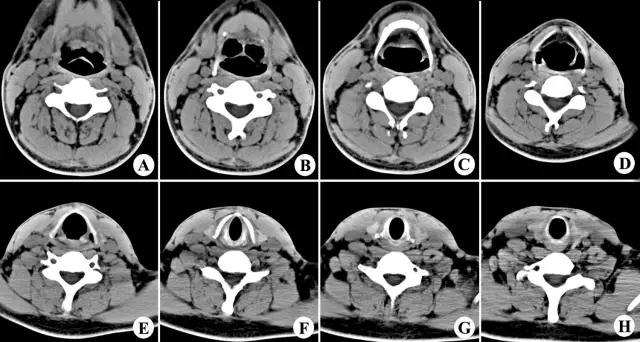

正常喉部CT

7、喉腔:

- 声门上区:声带之上,室带以上喉腔称为喉前庭。声带与室带之间的腔隙为喉室。室带(假声带),由室韧带、肌纤维及粘膜组成,前端起于甲状软骨前角的上中段内面,后端止于杓状软骨前上面。

- 声门区由声带构成,喉室下方由声韧带、肌纤维和粘膜构成,前端起于甲状软骨前角中段内面,后附着于杓状软骨声带突,厚约5mm。张开时出现一个等腰三角形裂隙称声门裂,发音时声带内收。

- 声门下区为声带下至环状软骨下缘以上的喉腔,正常气道与环状软骨间粘膜厚度不超过1mm。

2、CT

1、常规采用横断面扫描,喉腔中轴与扫描线垂直;

2、扫描范围自环状软骨下缘至下颌角会厌上缘,层厚3-5mm;

3、发音状态扫描:让病人连续发“E“音,这时声带内收,可较好显示声带、梨状窝、咽后壁及杓会厌壁的形态及病变。

2、CT、MRI检查